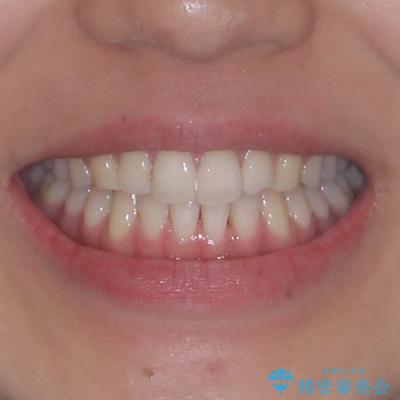

前歯の重なりをインビザライン・モデレートで矯正治療

- 20代女性

- インビザライン・モデレート

- 1年2ヶ月

- 治療費の目安: 65万円(税込)費用は治療当時の料金となります